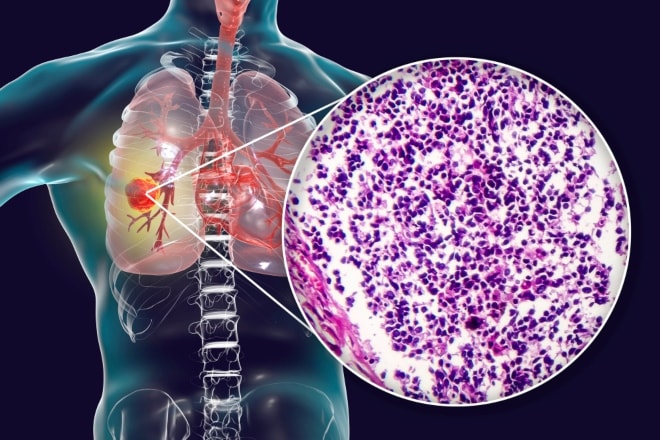

Meer dan de helft van de patiënten met longkanker heeft al uitzaaiingen als de diagnose wordt gesteld. Welke soorten longcarcinomen zijn er, wat zijn de stadia en welke prognose hoort daarbij? Een overzicht.

Meer dan de helft van de patiënten met longkanker heeft al uitzaaiingen als de diagnose wordt gesteld. Welke soorten longcarcinomen zijn er, wat zijn de stadia en welke prognose hoort daarbij? Een overzicht.